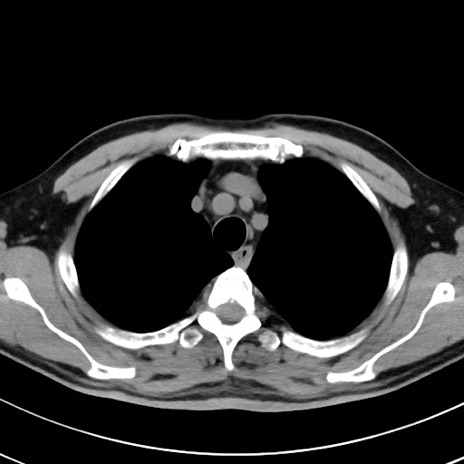

【腹部TIPS】症例29 参考症例 CT(横断像)

症例

70歳代男性